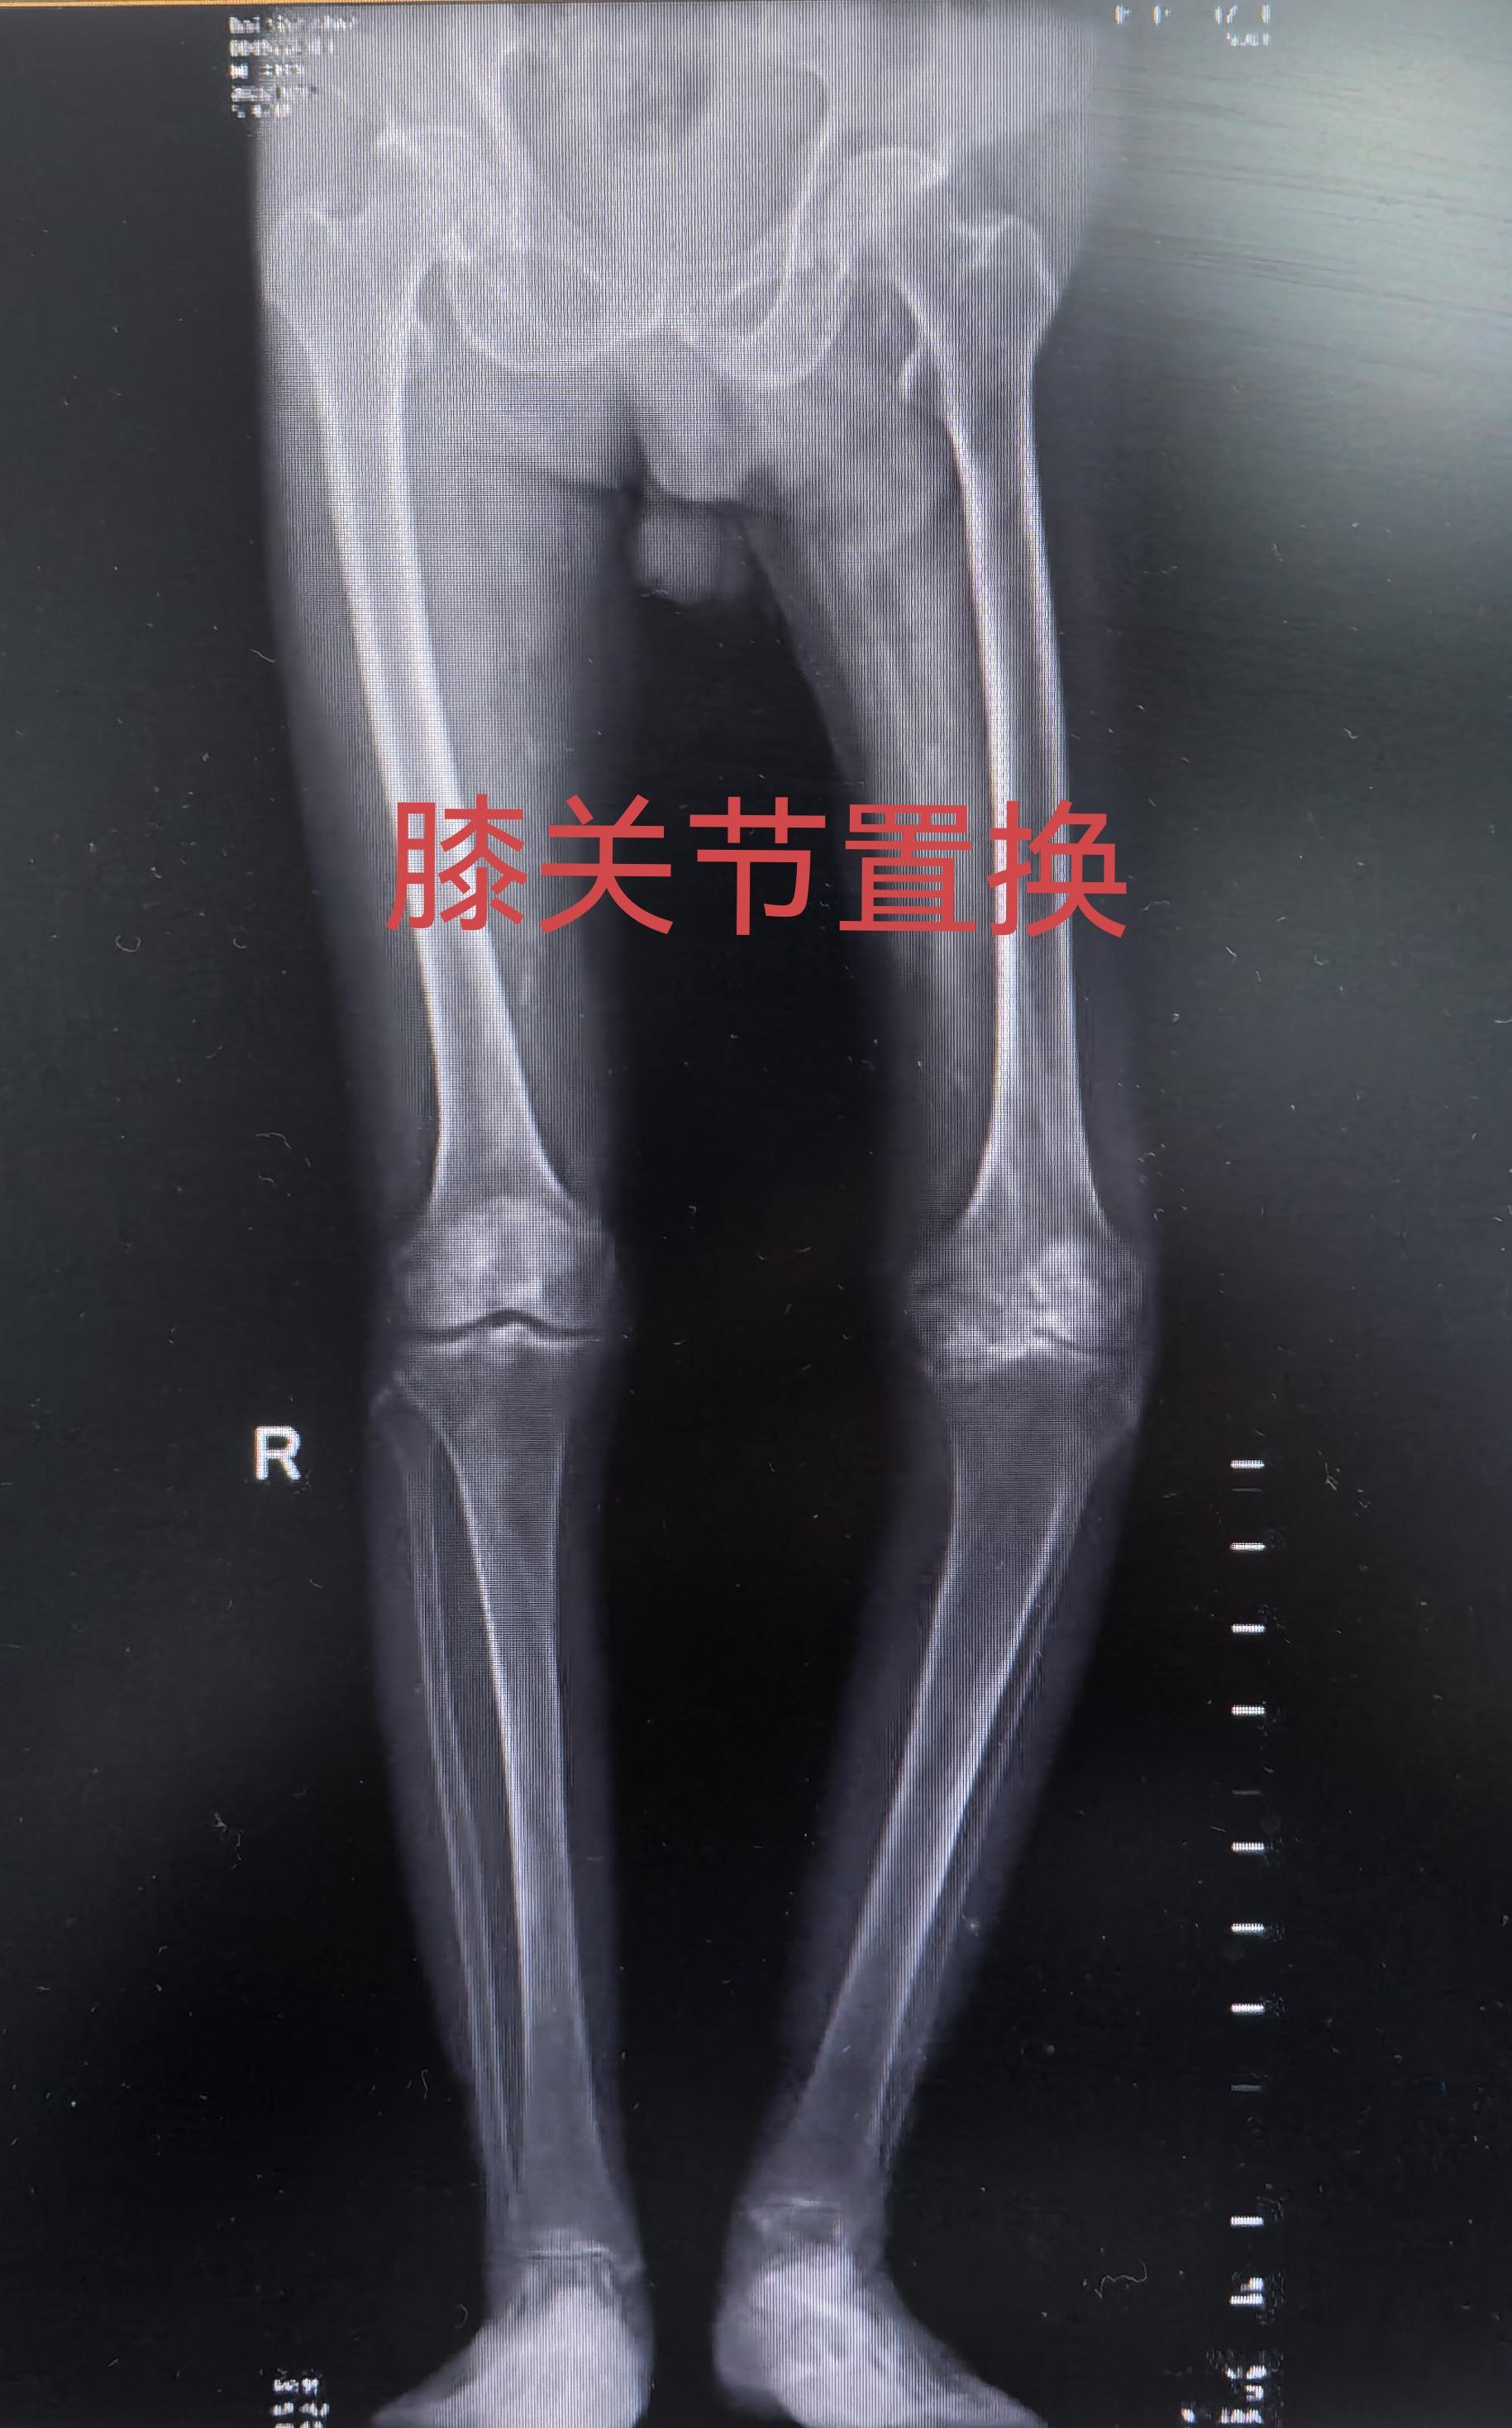

创伤性关节炎,膝关节置换。19岁胫骨平台骨折畸形愈合,未处理,现52岁...